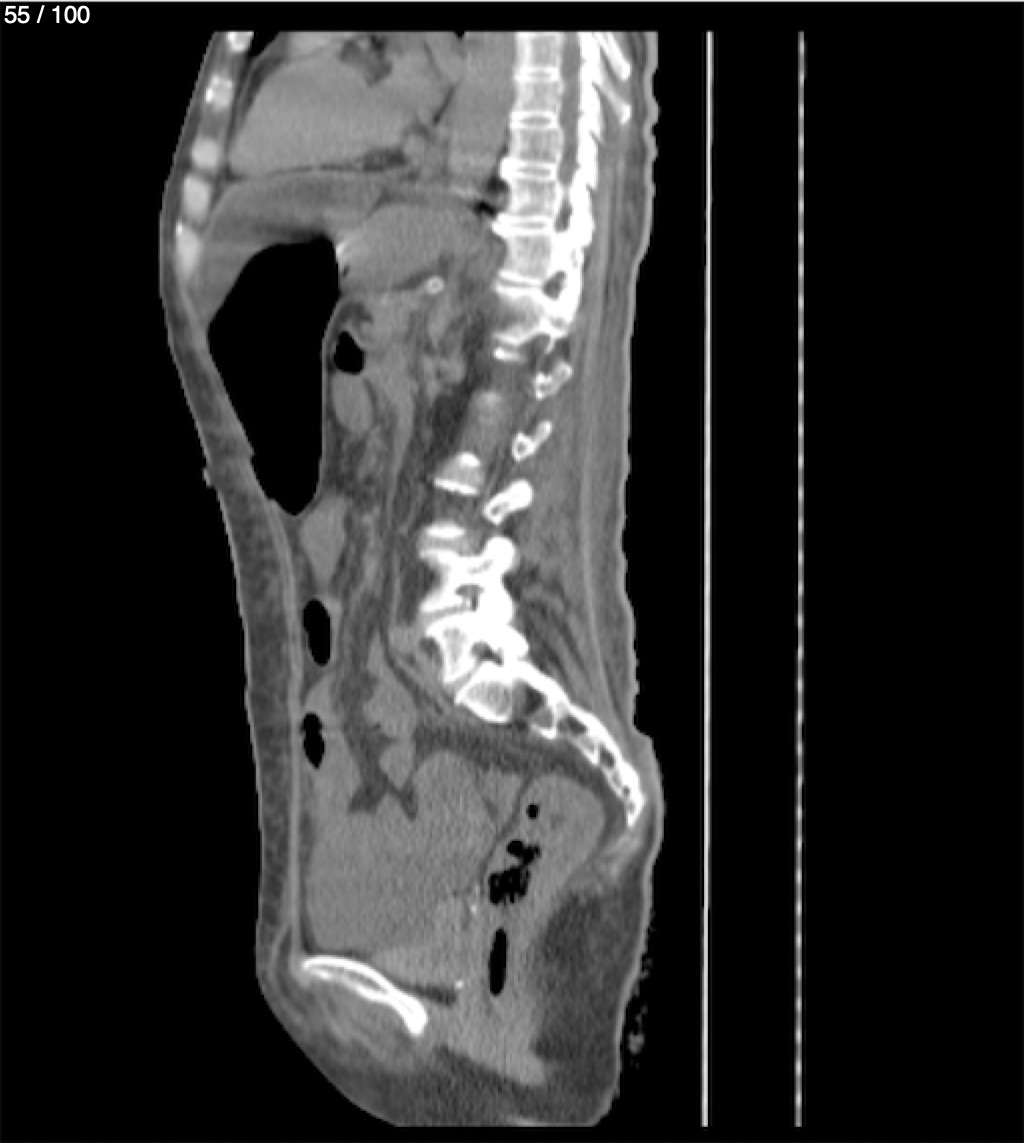

Hilda Geronimo Mendez 60A - T.C Abdomen Simple